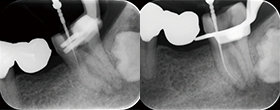

• Edge GlidePath™、EdgeTaper Platinum™、EdgeSequel Sapphire™を使用して二重湾曲根管の形状を残したまま、根管形成を行った例。

エッジグライドパスを使用

Edge GlidePath™

エッジテーパープラチナムを使用

EdgeTaper Platinum™ in MB